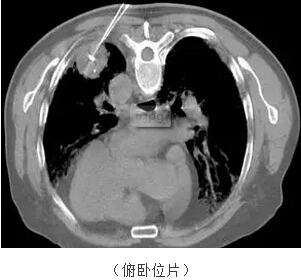

劉老先生家住株洲攸縣,身體不適到醫(yī)院檢查發(fā)現(xiàn)肺部有一個(gè)5*8cm大小的腫塊,老先生年齡大,患冠心病、糖尿病多年,體質(zhì)不好,幾個(gè)兒子非常孝敬,卻苦于無(wú)計(jì)可施,聽一位曾在株洲市腫瘤醫(yī)院腫瘤二科住院治療過(guò)的老鄉(xiāng)介紹該科擁有肺部微波消融治療的技術(shù),痛苦小,就帶著老人來(lái)就醫(yī),我們隨即給老人實(shí)施了這一微創(chuàng)消融治療。

我們?cè)贑T引導(dǎo)下將專用消融細(xì)針插入腫瘤內(nèi)部,CT的引導(dǎo)避免了可能出現(xiàn)的大出血、氣胸等損傷。

僅僅8分鐘就完成了這個(gè)5*8cm的大腫瘤的消融治療,細(xì)心的可以看到腫瘤內(nèi)密度明顯降低了,表明得到了消融?;颊咝g(shù)后恢復(fù)了正常的飲食和活動(dòng)。